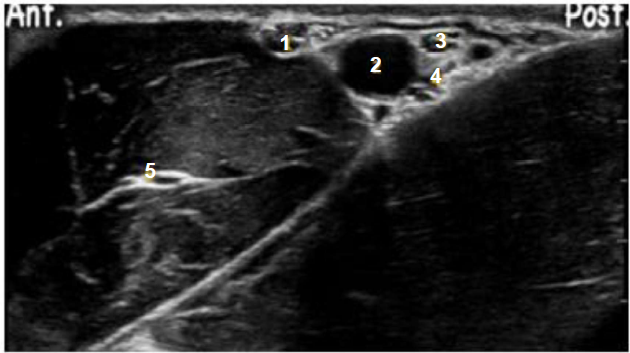

Em relação às técnicas de abordagem de anestesia do plexo braquial, para cirurgias do membro superior, a abordagem axilar é muito aplicada para cirurgias de fraturas do membro superior, sobretudo distais, e confecção de fístulas artériovenosas para realização de hemodiálise.

Baseado na janela ultrassonográfica para essa técnica, relacione a estrutura indicada na imagem à respectiva descrição.

| Estrutura | Descrição |

|---|---|

| (1) Estrutura 1 | ( ) Nervo radial |

| (2) Estrutura 2 | ( ) Nervo musculocutâneo |

| (3) Estrutura 3 | ( ) Artéria axilar |

| (4) Estrutura 4 | ( ) Nervo mediano |

| (5) estrutura 5 | ( ) Nervo ulnar |

A sequência correta dessa associação é: